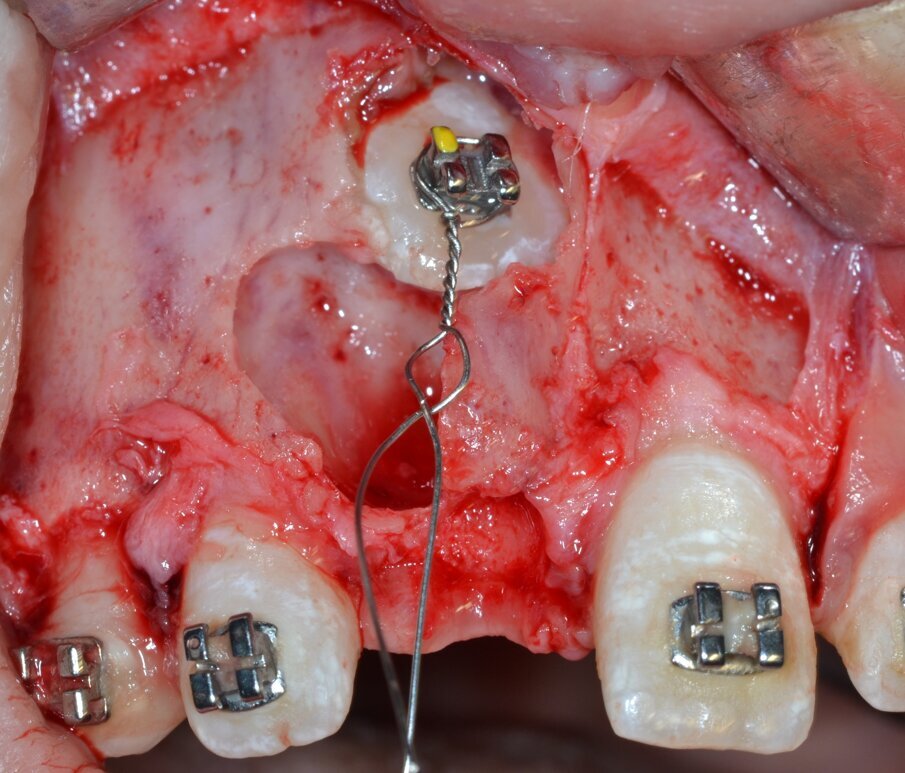

Si procede al clivaggio e all’enucleazione in toto della massa neoformata mediante una leva dritta (Fig. 9) seguita da un’accurata revisione chirurgica della cripta ossea residua (Fig. 10). Il pezzo operatorio viene inviato per l’esame istologico, che confermerà in via definitiva la diagnosi di odontoma composto (Figg. 11, 12). Poiché il piano di trattamento prevede di eseguire l’ancoraggio ortodontico dell’elemento ritenuto nella stessa seduta operatoria, la corona dentaria dell’elemento 1.1 viene esposta chirurgicamente per mezzo di un inserto piezoelettrico dedicato montato su un manipolo ad ultrasuoni (ES010T Esacrom Srl, Imola, Italia) (Fig. 13).

Si procede all’esecuzione dell’alveolectomia conduttrice (Figg. 14, 15) allo scopo di facilitare la trazione ortodontica mediante inserto dedicato montato su dispositivo piezoelettrico (ES009ST Esacrom Srl, Imola, Italia) e, successivamente, all’adesione del bracket ortodontico sulla corona dell’elemento 1.1 (Figg. 16, 17). L’ ultimo tempo operatorio prevede il riposizionamento e la sutura del lembo (Fig. 18) con punti staccati in Nylon 5/04 seguito dal riposizionamento in sede del filo ortodontico (Fig. 19).

Fig. 13_Esposizione chirurgica della corona dentaria di 1.1.

Fig. 14_Esecuzione dell’alveolectomia conduttrice mediante inserto piezoelettrico.

Fig. 15_Corona dentaria dell’elemento 1.1 correttamente esposta.

Fig. 16_Fasi di adesione per la cementazione di un attacco ortodontico.

Fig. 17_Attacco ortodontico cementato e applicazione del mezzo di trazione.